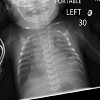

Case Presentation: A 3-week-old neonate presented with tachypnea, cough, and reluctance to feed. Work-up found bilateral chylous pleural effusion. The patient was initially managed conservatively with bilateral tube thoracostomies and octreotide, however output from chest tubes did not subside. A left thoracotomy was performed with wedge biopsy of the apical segment of the left inferior lung lobe and multiple titanium clips were used to control thoracic duct. Postoperatively the patient continued to have high chest tube output, despite placement of clips. Histology of the biopsy confirmed the diagnosis of congenital pulmonary lymphangiectasia.